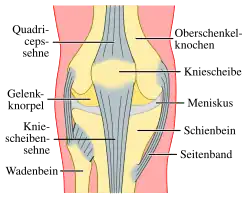

Das Kniegelenk (lateinisch Articulatio genus) ist das im Knie (lateinisch Genu, altgriechisch γόνυ gony) befindliche größte Gelenk der Säugetiere. Der Oberschenkelknochen (Femur), das Schienbein (Tibia) und die Kniescheibe (Patella) bilden dabei die knöchernen Gelenkkörper.

Das Kniegelenk ist ein zusammengesetztes Gelenk. Es besteht aus zwei Einzelgelenken, dem Kniescheibengelenk (Articulatio femoropatellaris), welches sich zwischen Oberschenkelknochen und Kniescheibe befindet, und dem Kniekehlgelenk (Articulatio femorotibialis), das zwischen Oberschenkelknochen und Schienbeinkopf (Caput tibiae) liegt. Anatomisch gesehen handelt es sich bei dem proximalen Gelenk zwischen Schienbein (Tibia) und Wadenbein (Fibula) (Articulatio tibiofibularis) zwar um ein eigenständiges Gelenk, das aber in der Regel über eine Ausbuchtung der Kniegelenkkapsel (Recessus subpopliteus) mit dem Kniegelenk verbunden ist.

Menisken

Da die miteinander in Verbindung stehenden (artikulierenden) Gelenkflächen nicht genau aufeinander passen, wird diese „Ungleichheit“ (Inkongruenz) durch halbmondförmige Faserknorpelscheiben, die Menisken ausgeglichen, die den Drehbewegungen folgen können. Eine weitere Aufgabe der Menisken besteht in der Vergrößerung der Kontaktfläche zwischen Schienbein und Oberschenkelknochen.

Man unterscheidet einen Innenmeniskus (Meniscus medialis), der C-förmig, größer und etwas unbeweglicher (da mit dem Innenband verwachsen) ist, und einen Außenmeniskus (Meniscus lateralis), der kreisförmig, kleiner und beweglicher ist (da er mit keinem Seitenband verwachsen ist). Die Menisken sind im Querschnitt keilförmig. Die hohe Kante liegt außen, die niedrige innen. Da die Oberschenkelknochen genau in der Mitte direkt auf dem Schienbeinplateau und peripher auf den Menisken aufliegen, tragen diese einen wesentlichen Teil der Last.

Bänder

Da das Knie durch seine knöcherne Konstruktion sehr instabil ist, wird es durch zahlreiche Bänder gesichert. Sie verstärken damit die Gelenkkapsel, in deren äußere Schicht sie in der Regel eingebaut sind. Die Bänder des Knies werden nach ihrer Lage in vordere (ventrale), seitliche (kollaterale), hintere (dorsale) und zentrale Bänder eingeteilt.